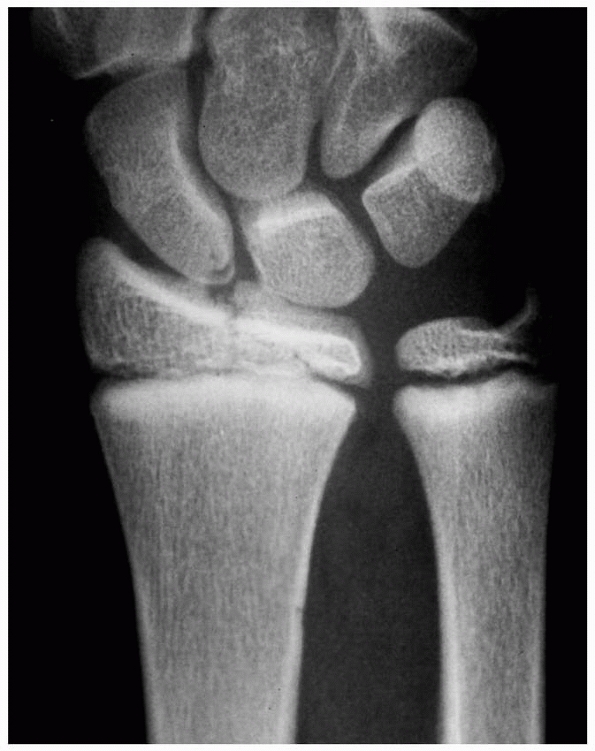

![]() |

FIGURE 9-31 A,B. A 10-year-old boy sustained a closed Salter-Harris type I separation of the distal ulnar physis (arrows) combined with a fracture of the distal radial metaphysis. C. An excellent closed reduction was achieved atraumatically. D. Long-term growth arrest of the distal ulna occurred.